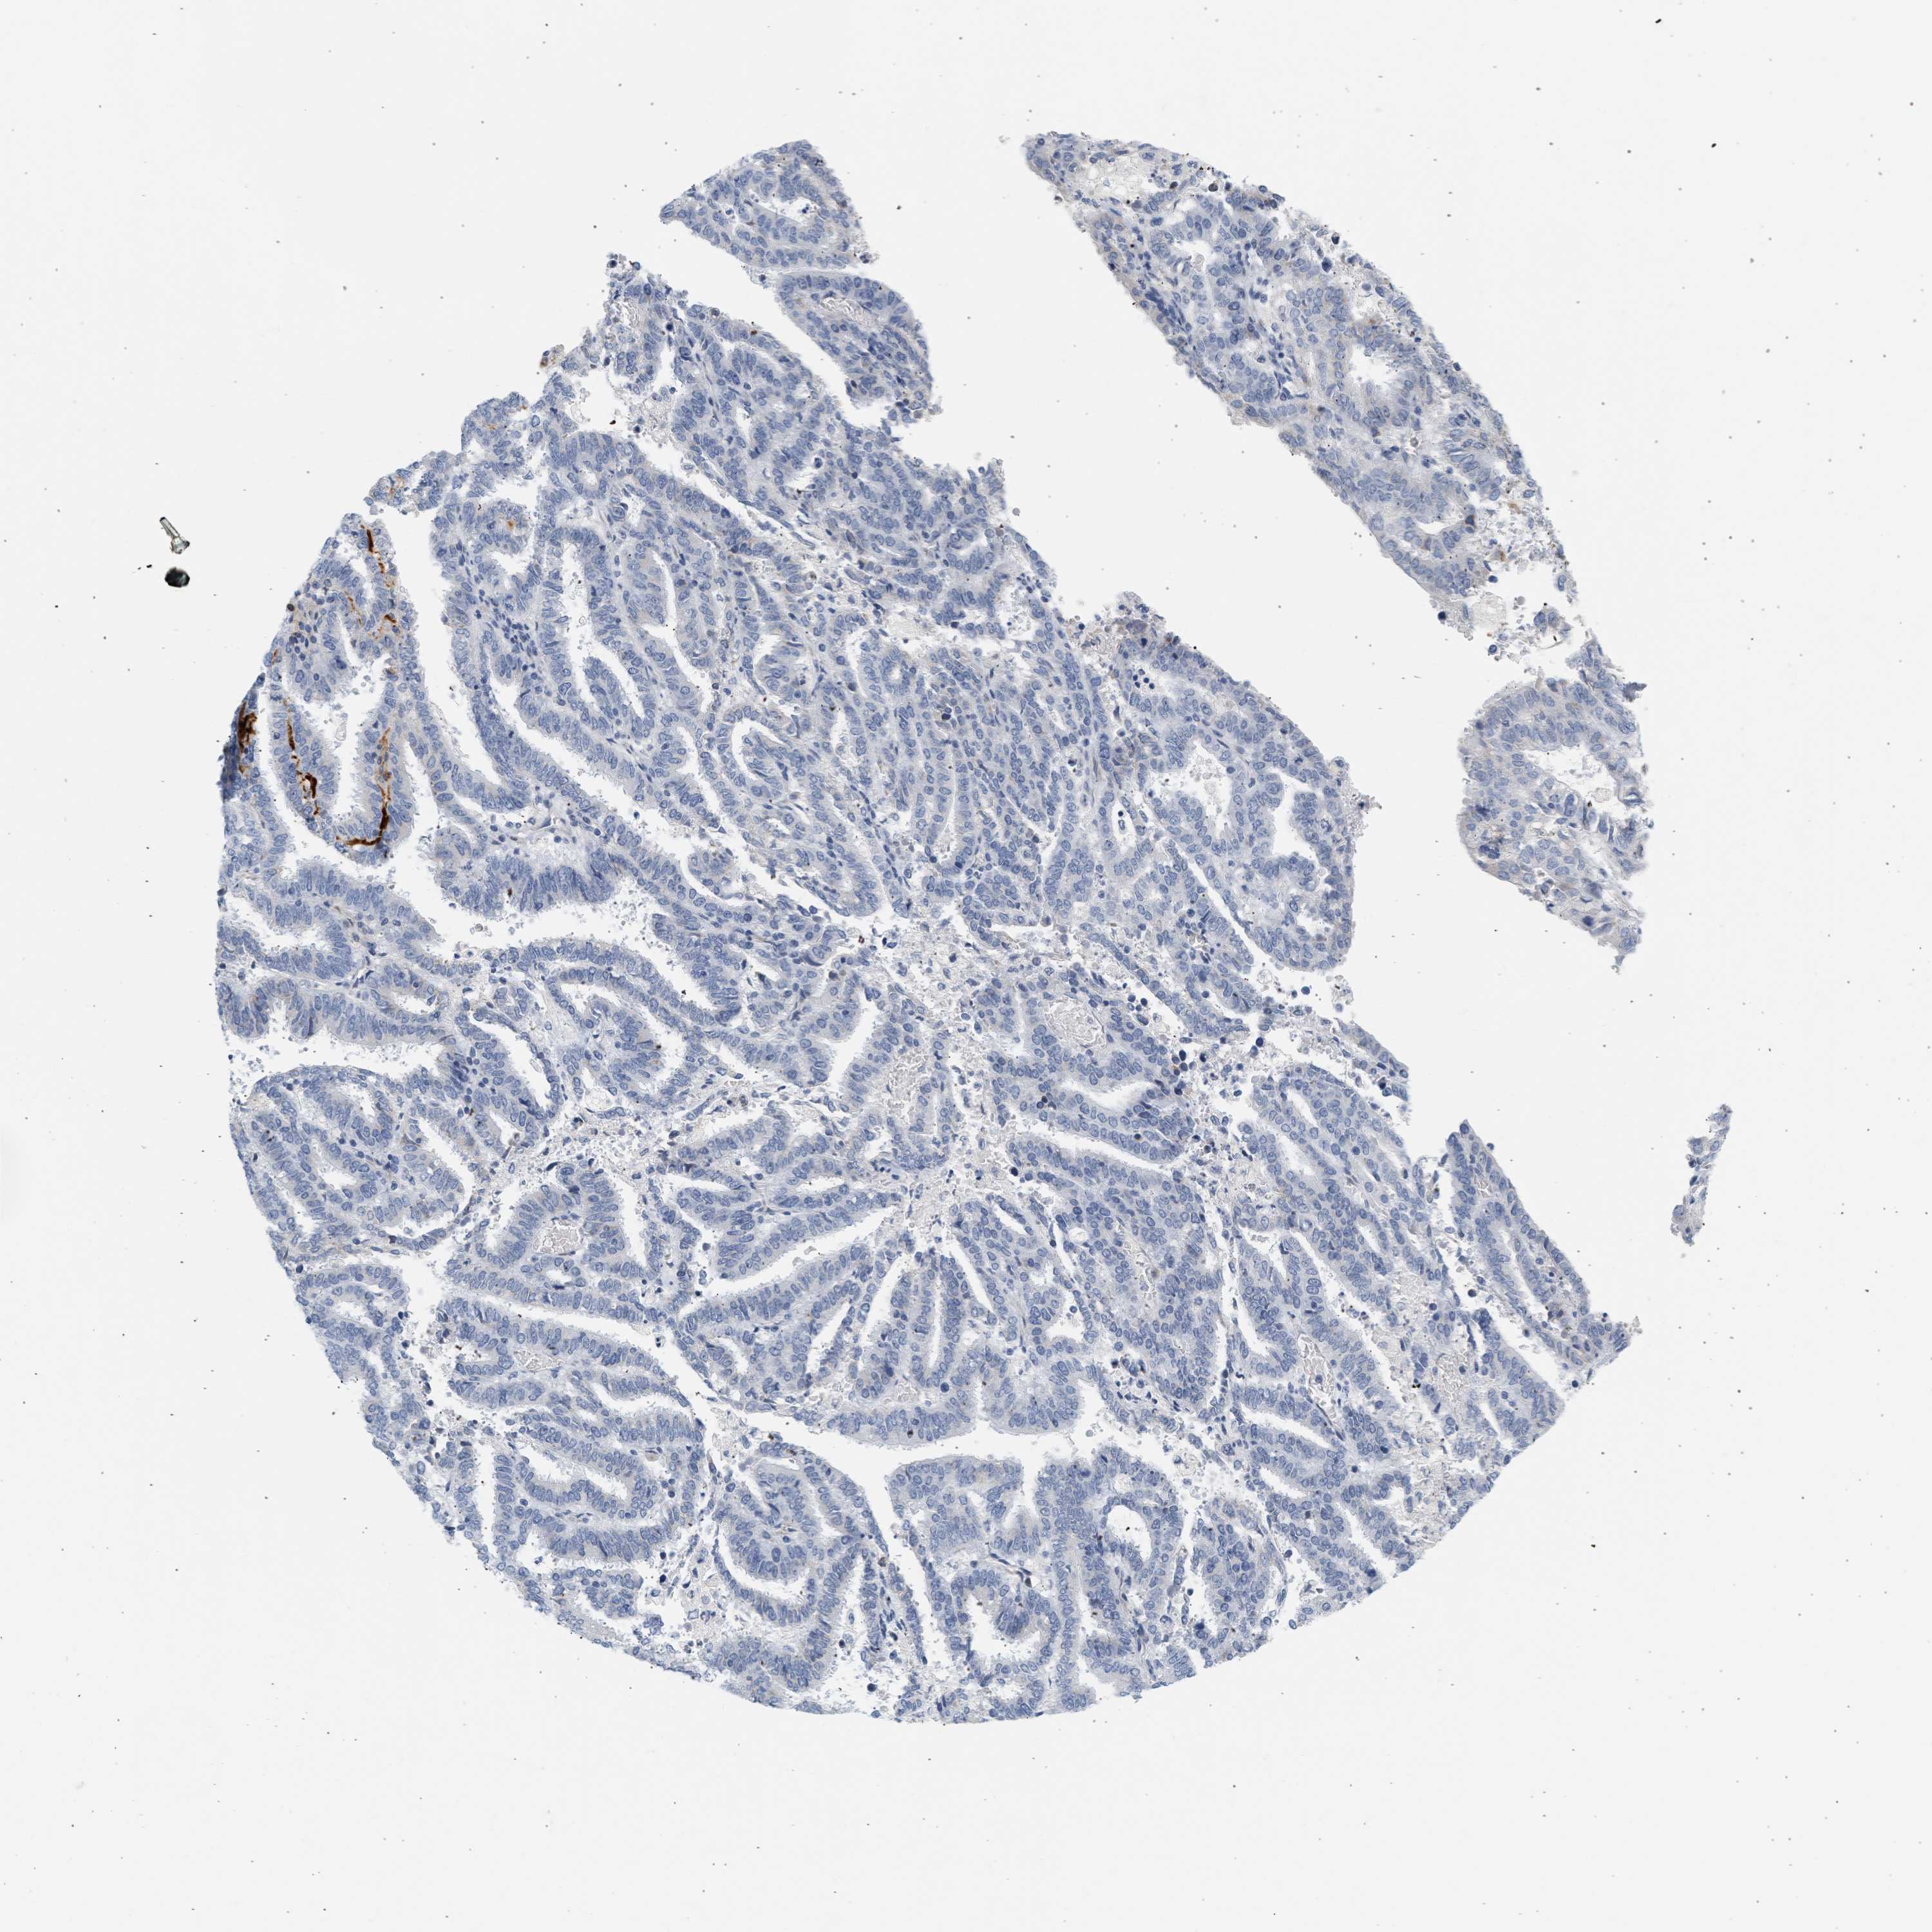

ENDOMETRIAL CANCER - Protein expressioni

A mouse-over function shows sample information and annotation data. Click on an image to view it in a full screen mode. Samples can be filtered based on level of antibody staining by selecting one or several of the following categories: high, medium, low and not detected. The assay and annotation is described here.

Note that samples used for immunohistochemistry by the Human Protein Atlas do not correspond to samples in the TCGA dataset.

Antibody stainingi

Antibody staining in the annotated cell types in the current human tissue is reported as not detected, low, medium, or high, based on conventional immunohistochemistry profiling in selected tissues. This score is based on the combination of the staining intensity and fraction of stained cells.

Each image is clickable and will lead to virtual microscopy that enables deeper exploration of all samples and also displays staining intensity scores, fraction scores and subcellular localization as well as patient and tissue information for each sample.

Antibody HPA018034

Staining

High

Medium

Low

Not detected

Intensity

Strong

Moderate

Weak

Negative

Quantity

>75%

75%-25%

<25%

None

Location

Nuclear

Cytoplasmic/membranous

Cytoplasmic/membranous,nuclear

Adenocarcinoma, NOS